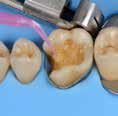

Why immediate dentine sealing?

Resin infiltration into the dentine surface is more effective on freshly cut dentine because it is uncontaminated and clean. Immedciate Dentine Sealing protects dentine against contamination with bacteria or remnants of temporary cements. It prevents post-operative sensitivity by sealing dentine tubules. It increases bond strength of the final indirect restoration to the tooth. It often eliminates the need for anaesthesia during the cementation procedure (when the restoration is delivered in the next appointment).

• Placing a rubber dam and isolating neighbouring teeth with teflon tape are always recommended.

• Use maximum air pressure to dry 1-PRIMER of G2-Bond to remove the solvent & residues of water.

• 1-PRIMER should be kept out of light as it contains photoinitiators.

• When doing immediate dentine sealing with G-Premio BOND, it is recommended to add a thin layer of G-aenial® Universal Injectable or a flowable composite on top.

1. Clean the tooth surfaces, rinse thoroughly and dry Apply G-Premio BOND Apply 1-PRIMER of G2-BOND Universal

5. Air dry to make a uniform bonding layer

4. Light cure

5. Fill in the undercuts with everX Flow®. Perform deep margin elevation if needed.

6. Remove unpolymerized layer. Expose enamel covered with adhesive with a fine grit diamond bur.

2A. G-Premio BOND

2B. G2-BOND Universal